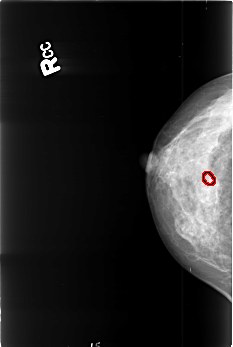

B_3419_1.RIGHT_CC

FILE: B_3419_1.RIGHT_CC.OVERLAY

TOTAL_ABNORMALITIES 1

ABNORMALITY 1

LESION_TYPE CALCIFICATION TYPE PLEOMORPHIC DISTRIBUTION CLUSTERED

ASSESSMENT 4

SUBTLETY 3

PATHOLOGY BENIGN

TOTAL_OUTLINES 1

BOUNDARY